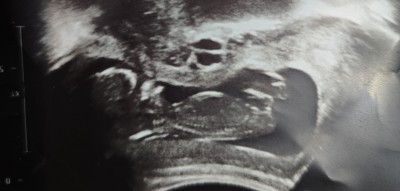

Kızlar bebeğimin cinsiyetini tahmin eder misiniz? Doktorum 13. Haftada gittiğimde söyledi ama, 18 de gittiğimde kendisini göstermiyor dedi, heyecanlıyım, sabırsızlanıyorum, emin olmak istiyorum

Gebelik haftası 21+3